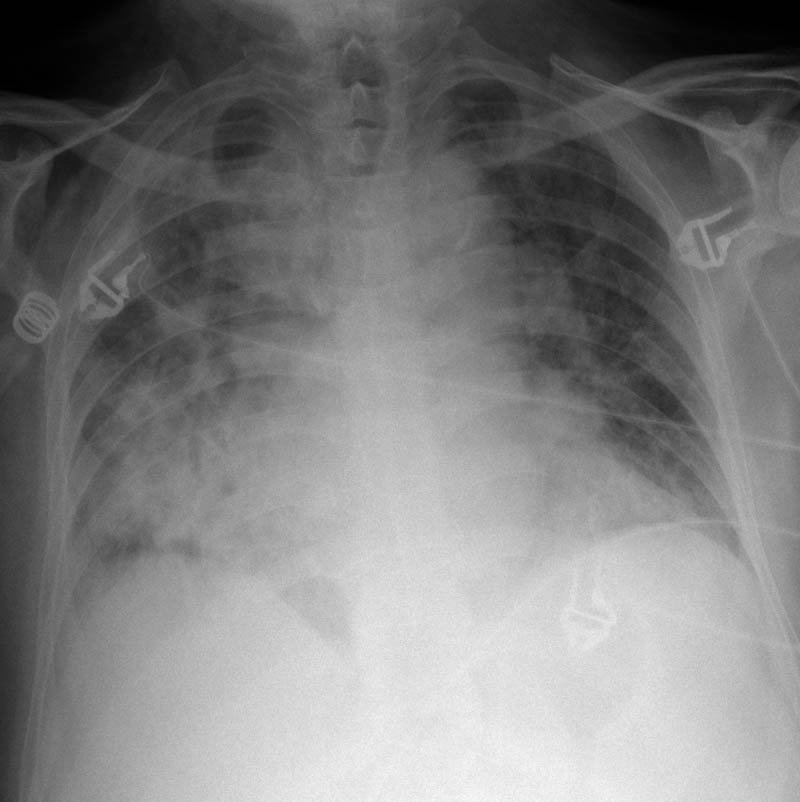

MO Distres respiratorio del adulto por trauma.